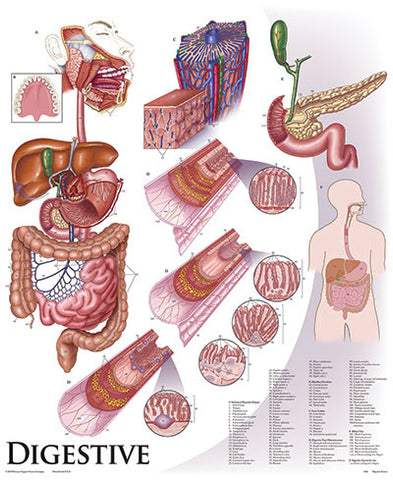

Anatomy

Anatomical models and charts by Body System or Anatomical Region for Nursing, Physical Therapy, and Medical Education.